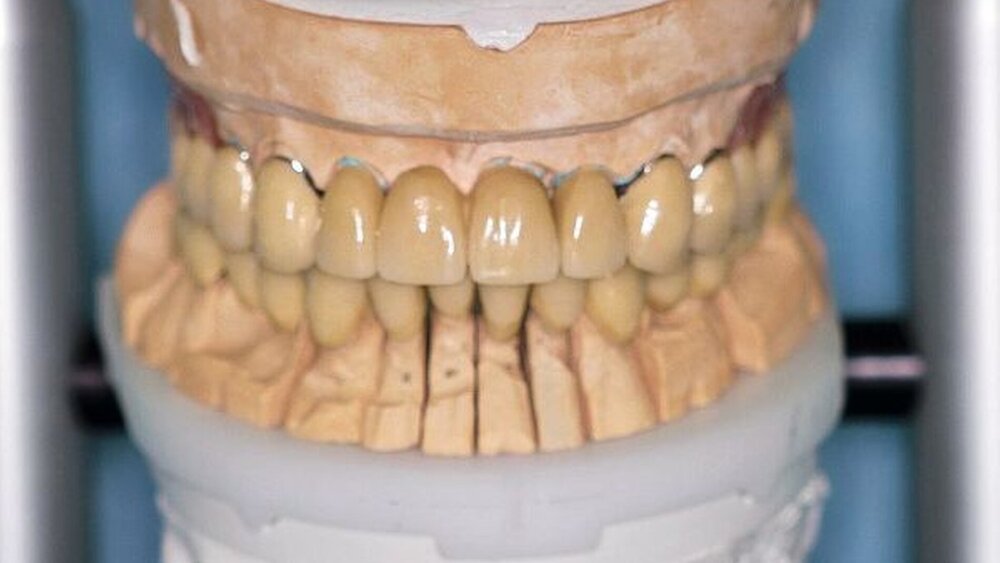

Nach durchgeführter Verblendung und Anfertigung des Sekundärgerüsts der partiellen oberen Prothese sowie Anfertigung einer separaten Wachsaufstellung wurden die Kronen und Brücken erneut anprobiert, um etwaige Änderungen die Farbe der Restaurationen betreffend vor dem Glasurbrand durchführen zu können. Zudem wurde die Sekundärkonstruktion der partiellen oberen Prothese auf ihre Passgenauigkeit hin überprüft. In einem letzten Schritt erfolgte dann die Beurteilung der Okklusion der Wachsaufstellung in Relation zu den angefertigten Kronen und Brücken.

In der darauf folgenden Sitzung wurden alle Kronen und Brücken sowie die teleskopgetragene, partielle obere Prothese für einen Zeitraum von sieben Tagen zum Probetragen mittels eines Zements auf Zinkoxid-Eugenol-Basis eingegliedert. Dem Patienten sollte durch das Probetragen der Restaurationen beziehungsweise des angefertigten Zahnersatzes die Möglichkeit gegeben werden, sowohl die Funktion beim Essen und Sprechen als auch die Ästhetik im sozialen Umfeld zu testen. Ein erneutes Entnehmen der Restaurationen wäre – für den Fall notwendiger Korrekturen – somit ohne Weiteres möglich gewesen. Da der Patient sowohl die Funktion als auch die Ästhetik betreffend keine Änderungswünsche vorbrachte und auch keine neuerlichen Beschwerden aufgetreten waren, konnten die Restaurationen nach besagtem Tragezeitraum von sieben Tagen entnommen, gesäubert und mittels eines Glasionomerzements definitiv befestigt werden. Im Anschluss wurden erneut Situationsabformungen der Kiefer genommen und der Patient erhielt nach erneutem Checkbiss-Registrat, eine okklusal adjustierte Stabilisierungsschiene im Unterkiefer. Diese dient der Therapie der beschriebenen Bruxismusproblematik und gewährleistet einen langfristen Erfolg der eingegliederten prothetischen Restaurationen (Abbildungen 13a, 13b, 13c, 14, 15a, 15b, 15c).